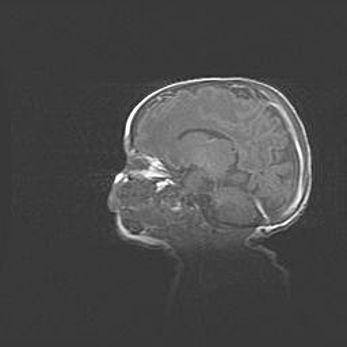

Церебральная ишемия II.

Возраст: 5 дней

Вес: 3400 г

Пол: женский

Окружность головы: 35 см

Срок гестации: 39 недель

Церебральная ишемия – это заболевание, характеризующееся недостаточностью (гипоксией) либо полным прекращением (аноксией) снабжения мозга кислородом по причине закупорки одного или нескольких сосудов. Это приводит к  что метаболическим расстройствам различной степени тяжести в тканях головного мозга, развитию коагуляционных некрозов и гибели нейронов.